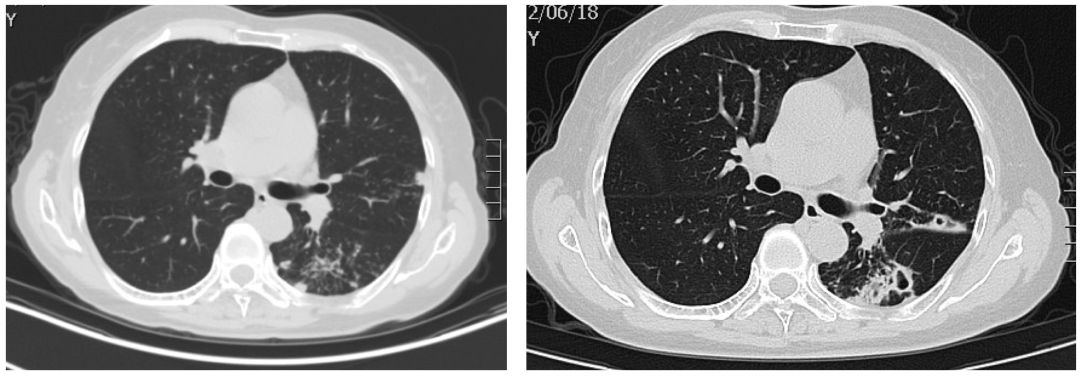

血Na133mmol/l,血常规:WBC 13.34*10^9/L,N% 91.3%,Hb 105.0g/L,PLT 237.0*10^9/L;CRP:15mg/L;心梗三项:高敏肌钙蛋白:0.016ng/ml↑,余正常;降钙素原:0.738ng/ml;心电图:1.窦性心律 2.T波改变(I、aVL、II、III、aVF、V4、V5、V6倒置)。 腹部CT(-),胸部CT如下。

该患者疾病诊断和病因究竟是什么?肺部感染吗?但患者肺部影像又没有看到显著感染征象,临床表现也不符合肺部感染,故肺部感染诊断不成立……患者高热、意识障碍伴有神经系统体征,诊断首先考虑中枢神经系统感染可能。

患者女性,66岁,反复咳嗽咳痰近3年。患者近3年来,多次查血沉基本正常,结核抗体阴性,结核杆菌T细胞检测(-),痰x-pert(-)。曾辗转多家医院就诊,均考虑肺结核,拟行抗结核治疗,患者拒绝接受肺结核诊断和抗痨治疗,症状时轻时重,症状重时就自行口服抗生素治疗。病因究竟是什么?是结核感染吗?该如何确诊?肺部CT如下:

左图:患病之初;右图:患病2年7月后